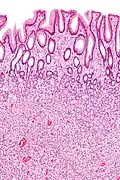

Hyperplastic polyp Colorectal (unless otherwise specified) Serrated unbranched crypts if polyps are more than 100

Hyperplastic polyp of the stomach Stomach Elongated, tortuous, and cystic foveolae separated by edematous and inflamed stroma.[14]